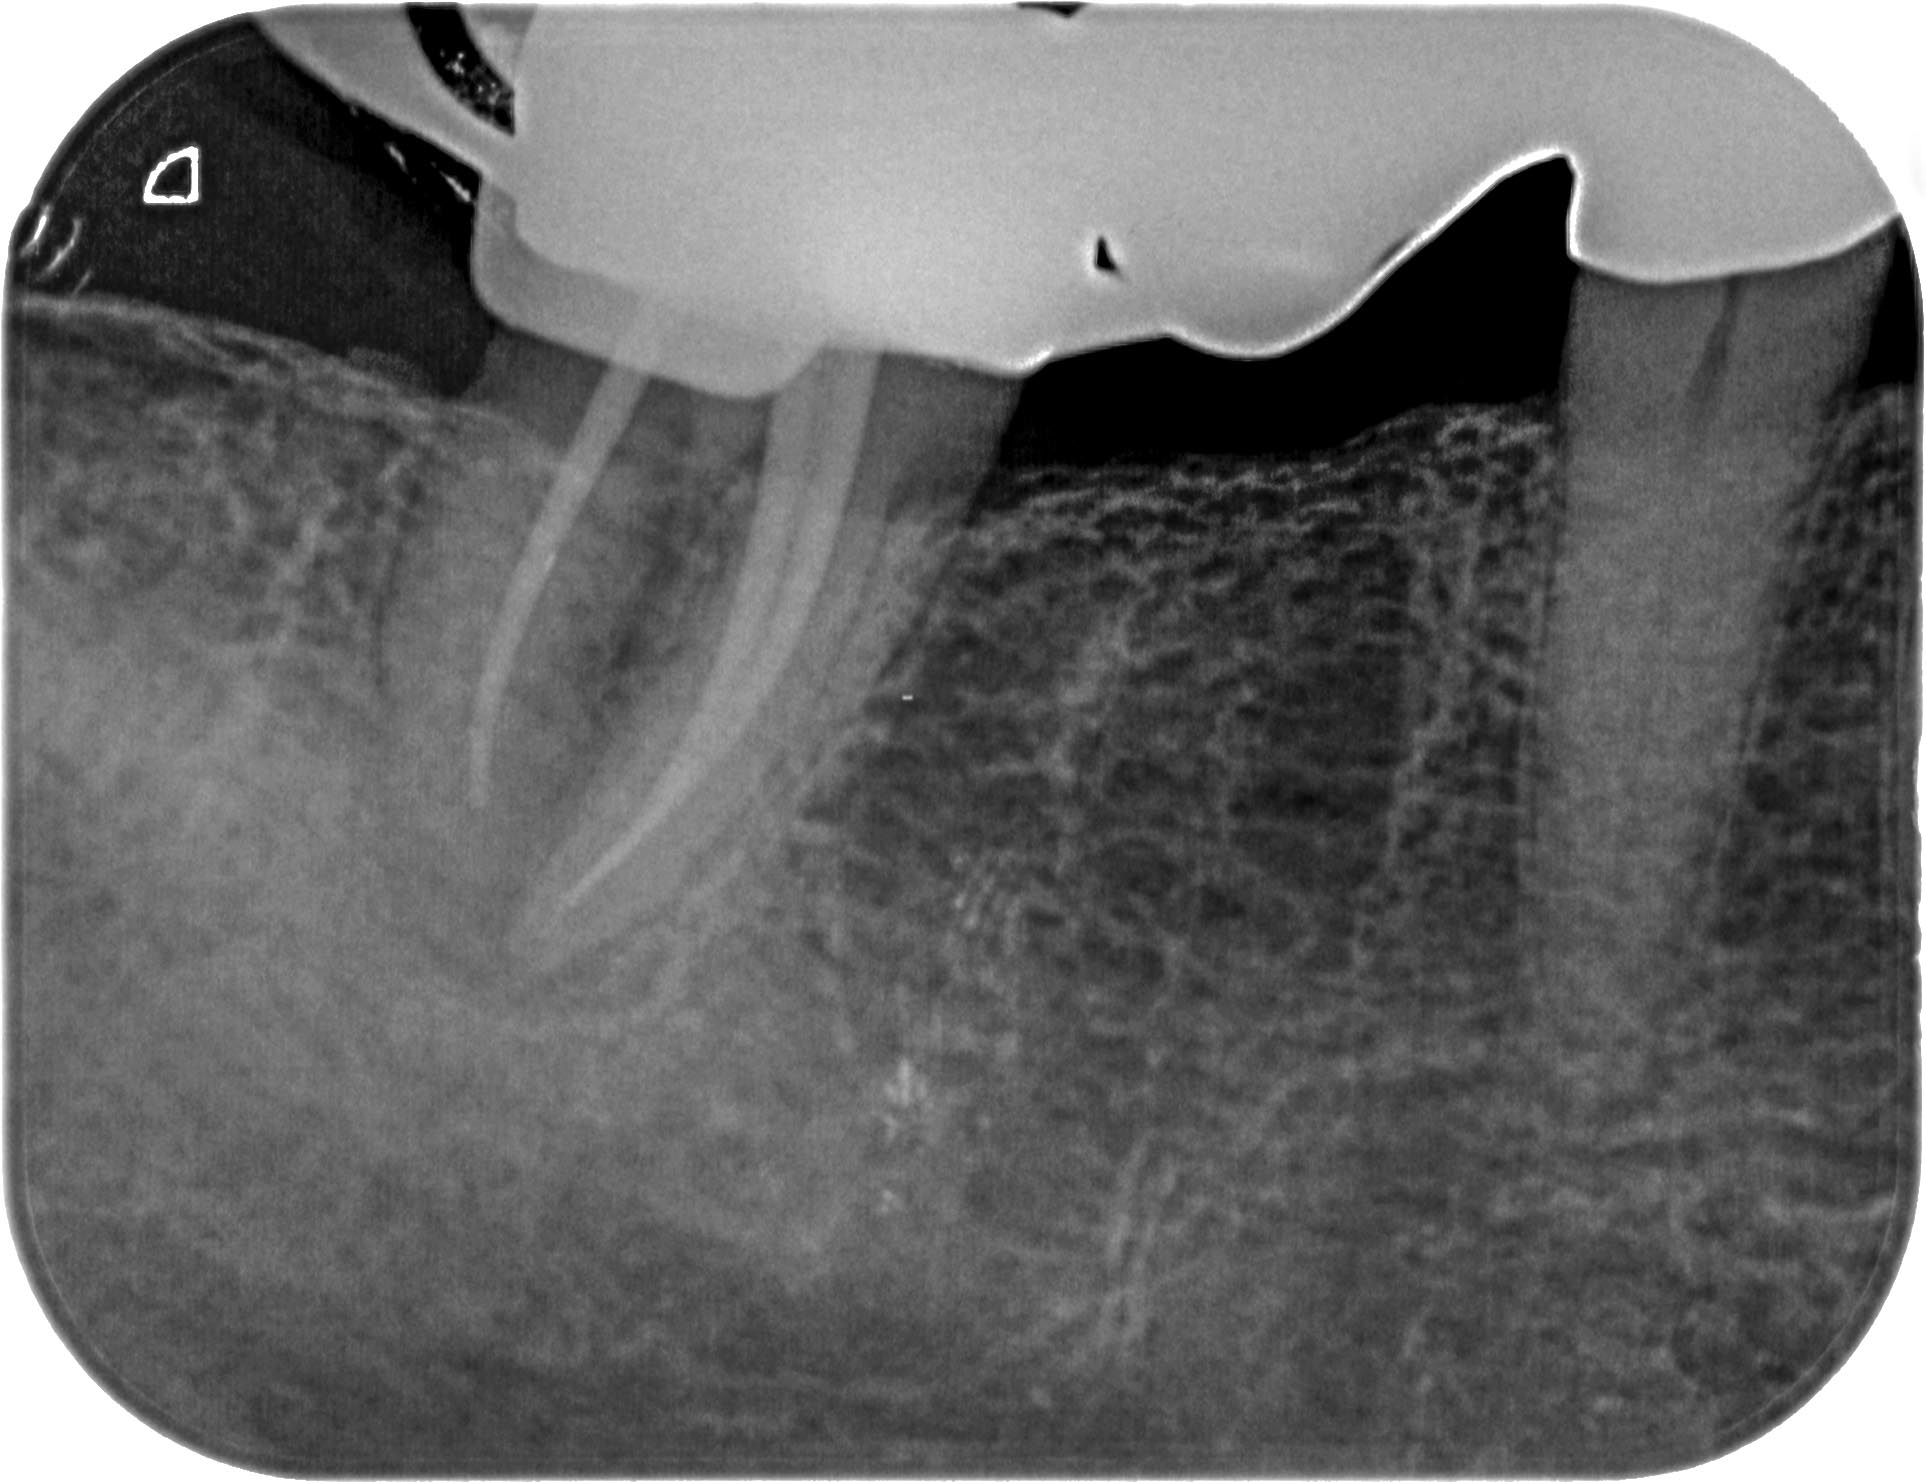

KF-1-3 Veröffentlicht 5. August 2013 am 1926 × 1482 in Unauffälliger Zahn 47 Zahn 47 Masterpoint- Aufnahme